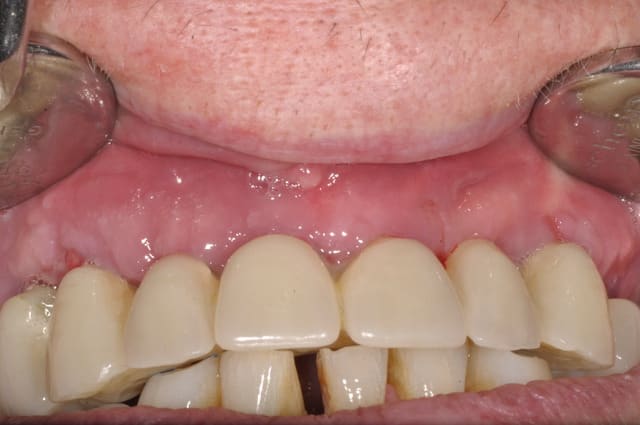

planif cas 1

Si tu as suivi les cas présentés depuis plusieurs années les bridges provisoires ont une armature métal pour la rigidité du fixateur externe, l’intervention se déroule en 1 seul temps chirurgical donc sans prise d’empreinte, c’est pour cela que je parle de MCI. Pour la passivité du bridge avec le système Nobel Guide et leurs piliers expansifs je n’ai vue aucun cas clinique présenté sur le forum. As-tu déjà utilisé le procédé ? Dans les cas présentés sur la vidéo, aucune clé de positionnement n’a été utilisée, le placement des piliers se fait selon la simulation implantaire assistée par ordinateur, leurs présentations a été faite en prospective par OTP, modèle 3D et à la demande de beotien la solution pilier fixe a été retenu à la place du bridge transvisé. Quel sont les compléments d’information que tu as besoin et ou la photo ne te suffi pas ? Pour le protocole d’une MCI, empreintes des maxillaires, dimension verticale de l’occlusion, définition de l’esthétique souhaitée, prescriptions, réalisation du Positscan, traitement des informations à partir des données DICOM, simulation implantaire assistée par ordinateur, validation, réception des DMSM selon les types d’implants et encastillages les procédures varient. Quel système implantaire utilise-tu ?

contrôle d'un des cas à 1 mois

Je viens de revoir au cabinet un des 3 cas, car la céramique de la 25 était fracturée.

J'ai pris une photo (iphone) avec le bridge déposé avant de mettre temporairement le bridge coping de Posit. Pas la peine de commenter le bas je n'en suis pas responsable.